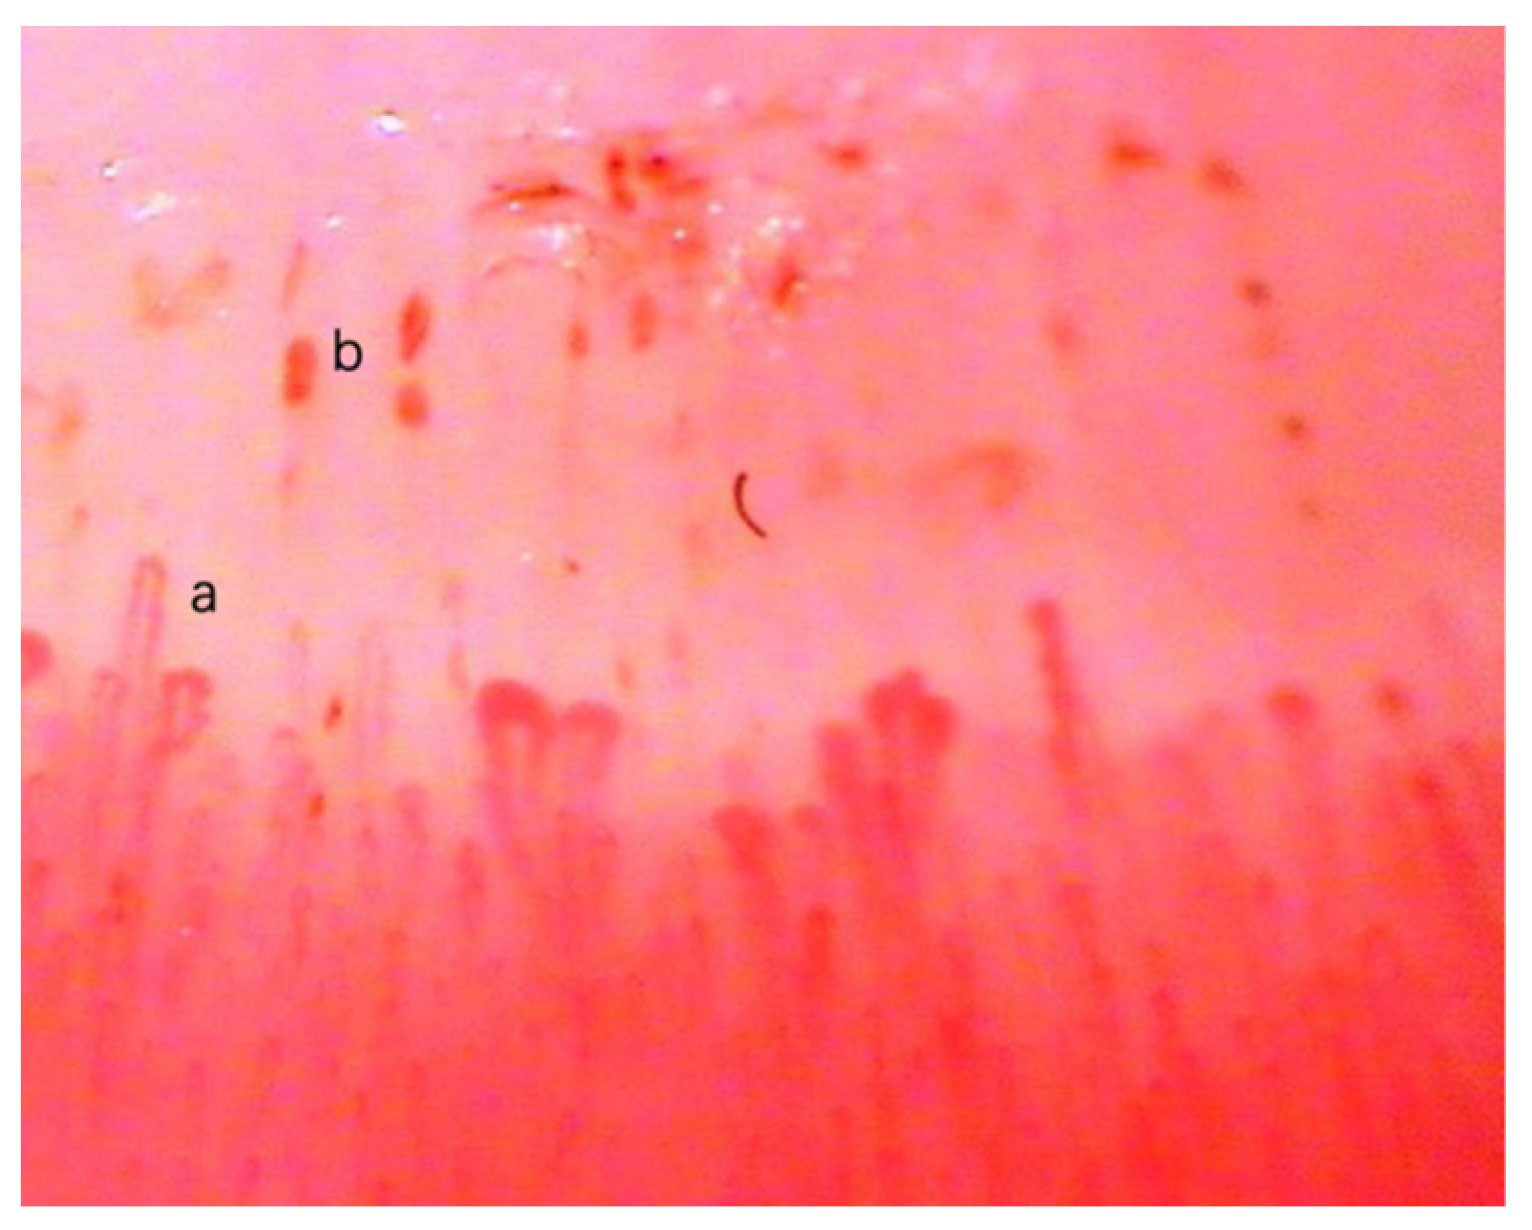

3.1. Data Collection and Preprocessing